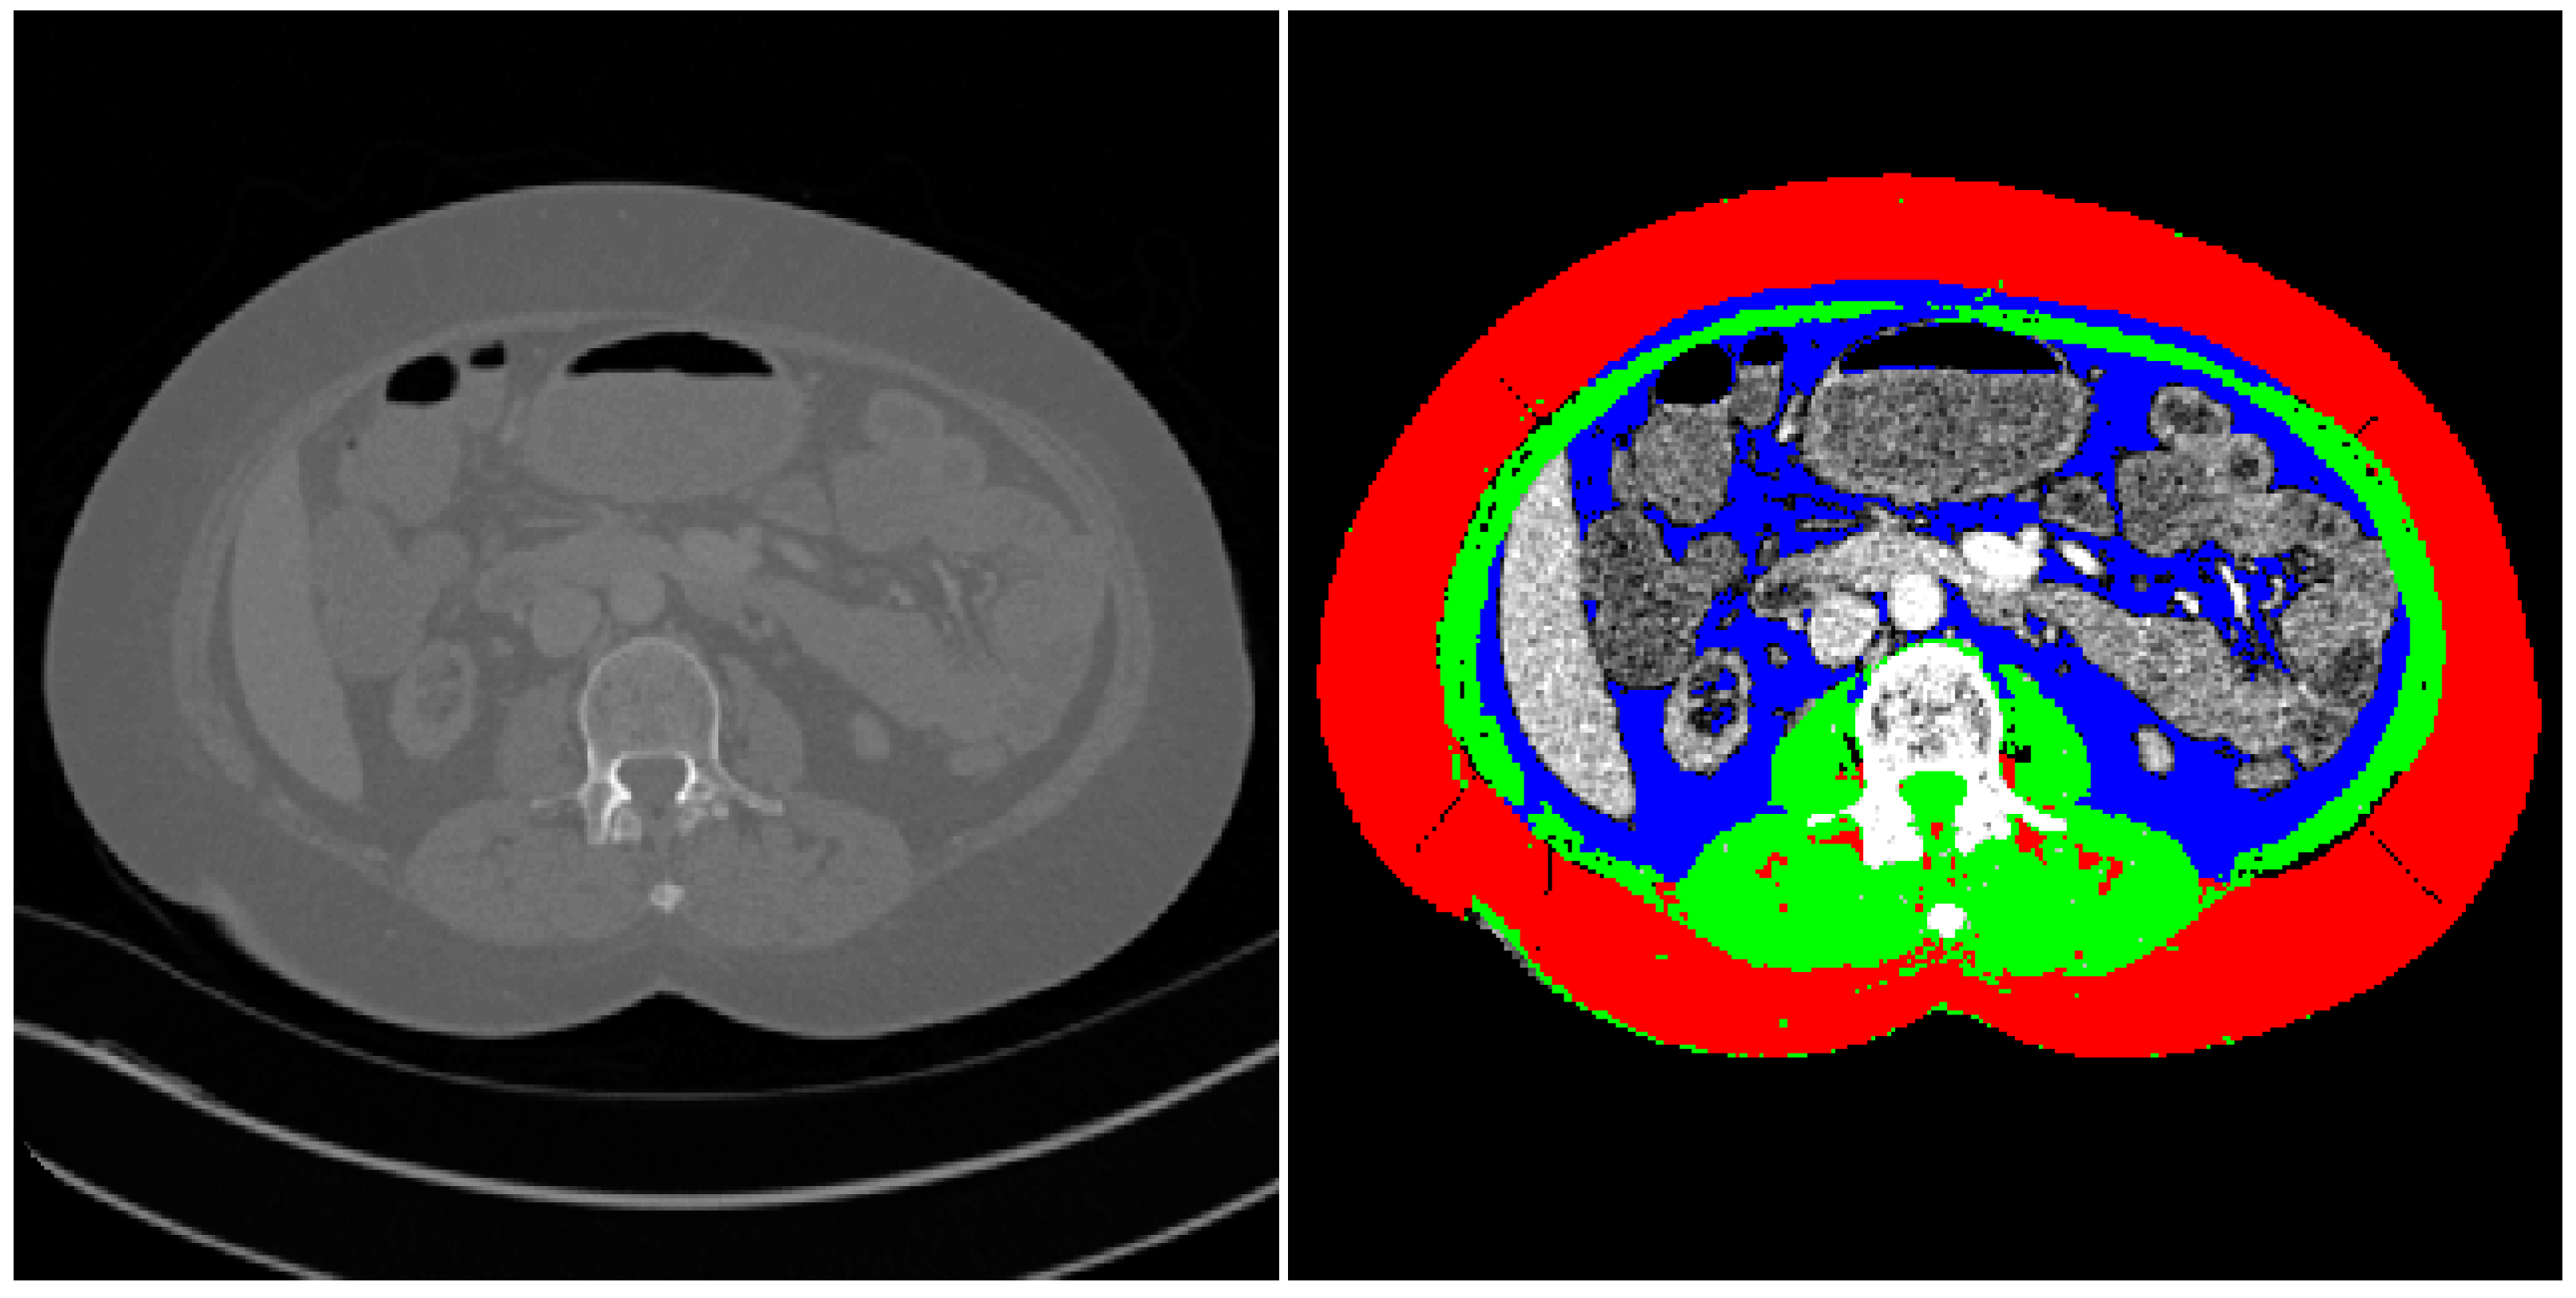

Sarcopenia was assessed using the semi-automated method previously described by Kim et al. [24]. Measurements were performed by two board-certified radiologists. The CT slice corresponding to the midpoint of the L3 vertebrae was identified and imported into the measurement application. The peritoneum was traced on these reference images to automatically identify skeletal muscle, visceral fat, and subcutaneous fat. All automated image analyses were prospectively assessed for accuracy to rule out miscalculations. Attenuation values of −29 to 150 Hounsfield units were assigned to identify muscle tissue (Figure 1).

Figure 1. A CT slice at the level of L3 used for assessment of sarcopenia. Points around the peritoneum were traced to enable segmentation of the imported CT slice (left) into the final image with a separating of skeletal muscle and visceral, subcutaneous fat (right). Red = subcutaneous fat, blue = visceral fat, and green = skeletal muscle.